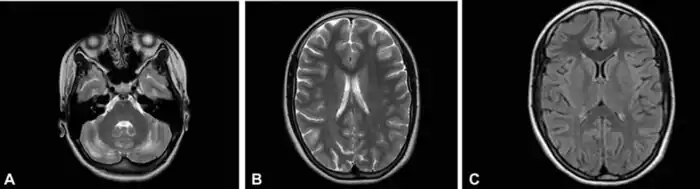

До и после возобновления терапии лейковорином при недостаточности ДГПР

- 1 2 Pappalardo MG, Di Nora A, Giugno A, Meli C, Sapuppo A, Pavone P, Fiumara A (September 2022). Dihydropyridine Reductase Deficiency: Acute Encephalopathy Related to Folinic Acid Treatment Interruption in a Girl. Global Medical Genetics. 9 (3): 247–251. doi:10.1055/s-0042-1756661. PMC 9484871. PMID 36132999.